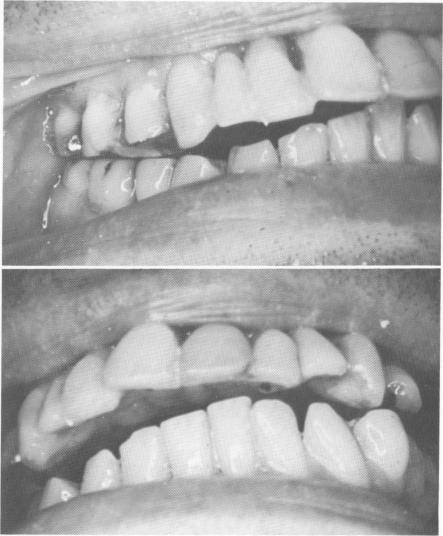

Fig. 15-38. A patient exhibiting an extreme overjet and flaring out of the anterior quadrant of teeth.

Fig. 15-39. The asymmetry of both arches is clearly visible.

1 Patient exhibits extreme overjet and flared upper anterior teeth

2 Asymmetry of maxillary and mandibular arches clearly visible